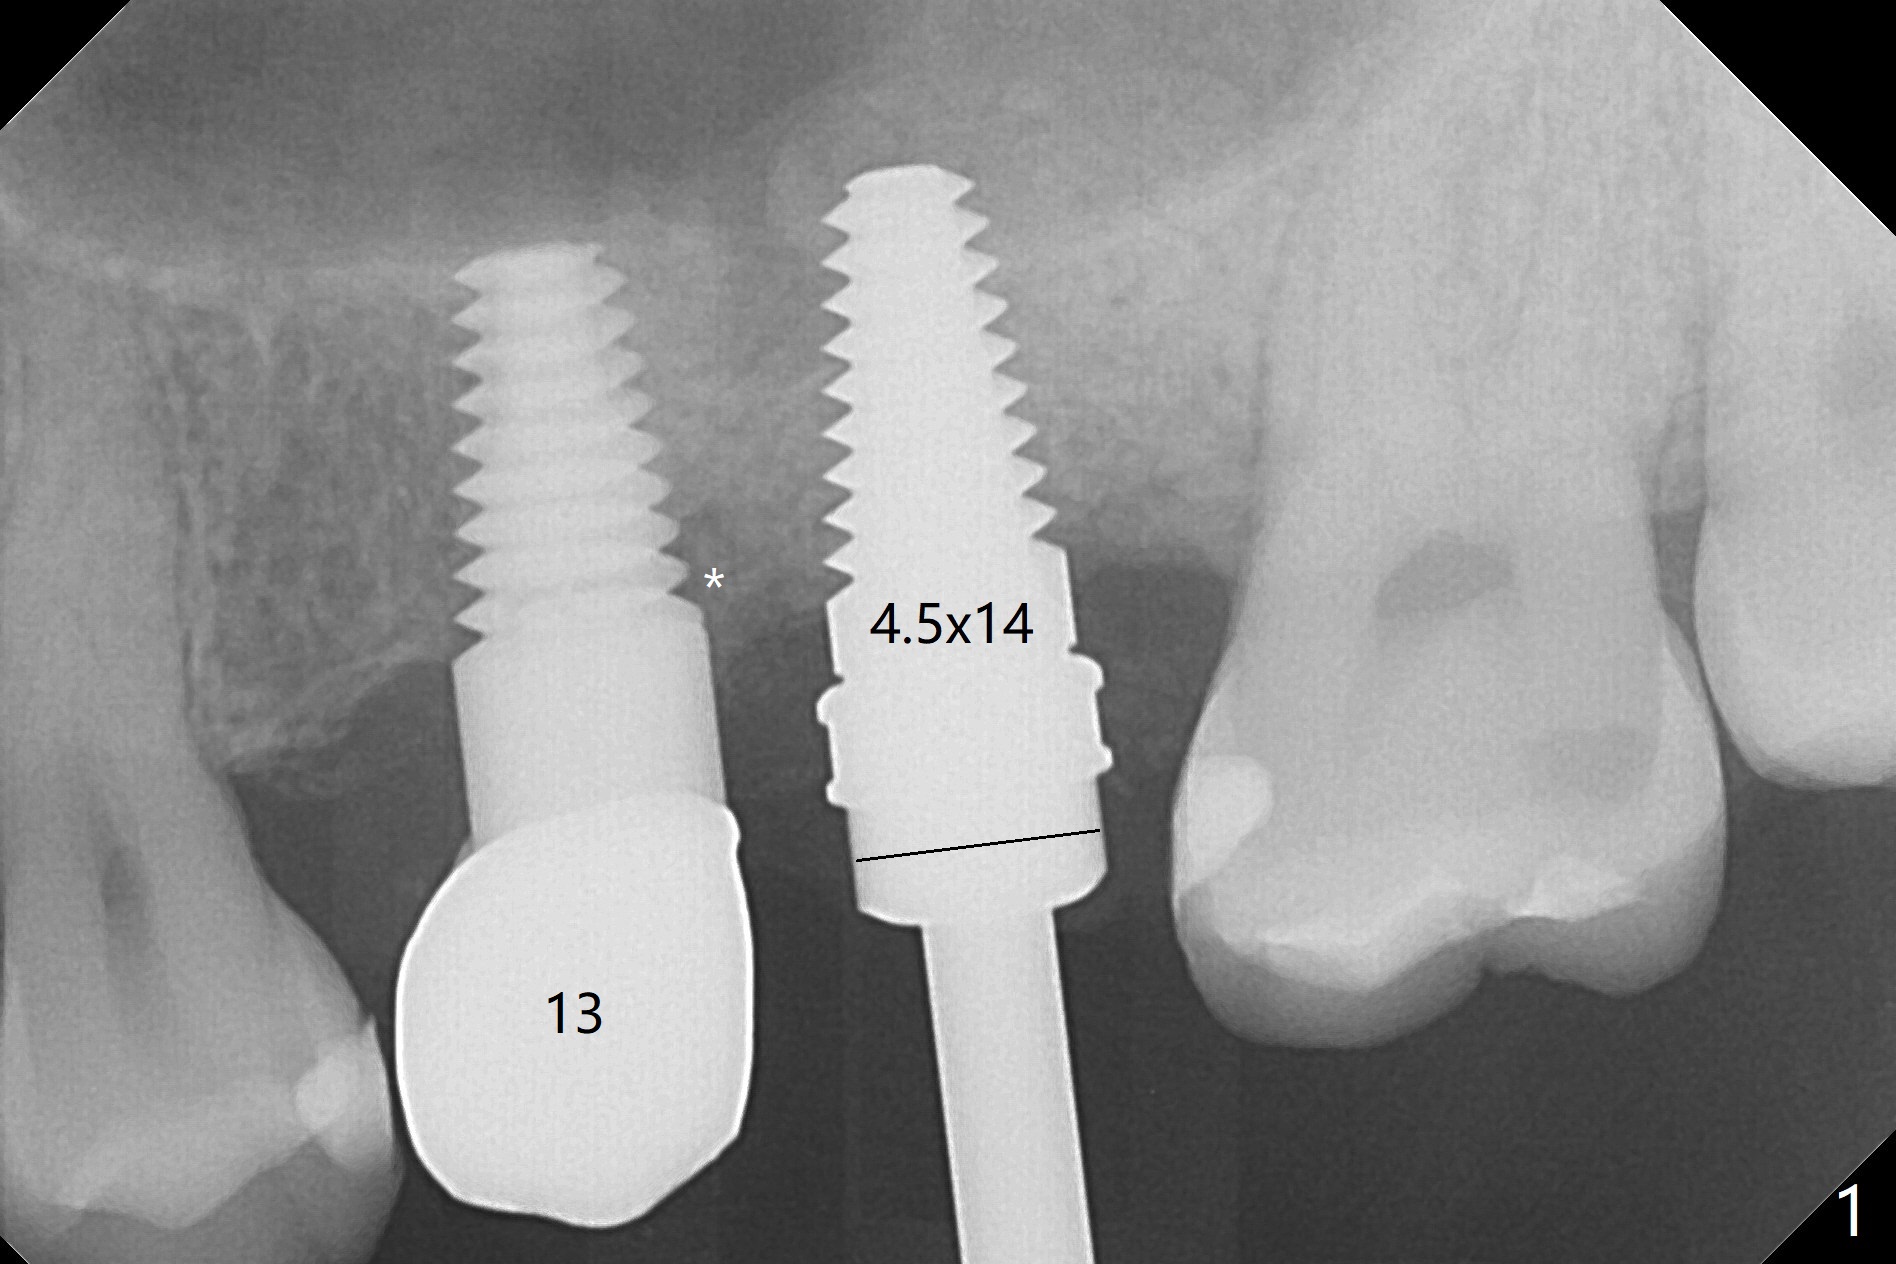

The ridge at #14 seems wide 6 months post implant removal and bone graft (before and after incision). In fact the palatal bone is low, which was the basis for periimplantitis. The new osteotomy is not initiated buccal enough. Immediate redo or guided surgery can avoid this complication. When a 4.5x14 mm tap is placed (Fig.1), the palatal threads are exposed. The buccal bone of the osteotomy has to be removed before placement of a 4.5x11 mm with 1 thread exposure palatal (Fig.2). Periimplantitis at #13 is found intraop (Fig.1 *). After removal of granulation tissue and use of Titanium brush, allograft is placed at #13 and 14 (Fig.2 ^) and is covered by PRF. Bone expansion is not conducted because of high bone density. If there is difficulty in restoration due to deep implant placement, it has to be backed up using torque wrench. The wound appears to heal by secondary intention 20 days postop (Fig.3). The implant is subgingival nearly 3 months postop (Fig.4 ^: gingival margin). It appears that the implant could be backed up (Fig.5,6). A 5 mm healing cuff is placed with Cetacaine and antibiotic ointment. The implant remains subgingival with the healing abutment 4 months postop. With Cetacaine and 2 gingival retraction cords, the implant margin is barely exposed. Large and deep gingivectomy is performed with Waterlase without too much pain. The gingival cuff is slightly erythematous and hemorrhagic on cementation (partially due to suboptimal oral hygiene, Fig.7). The margin is deep. Tatum implants are contraindicated when the gingiva is thick (Fig.8).